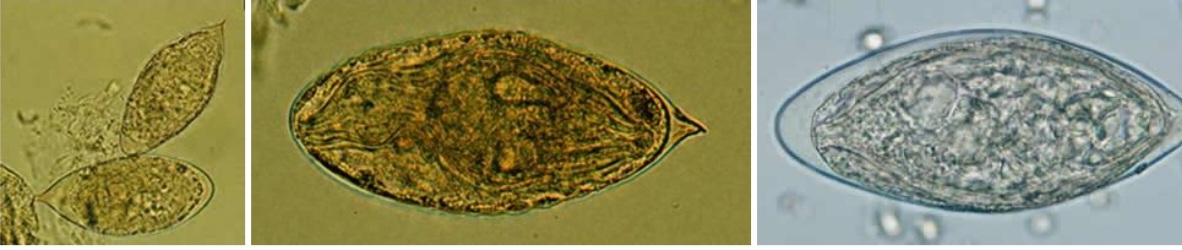

Schistosoma haematobium ( esquistosomiasis)